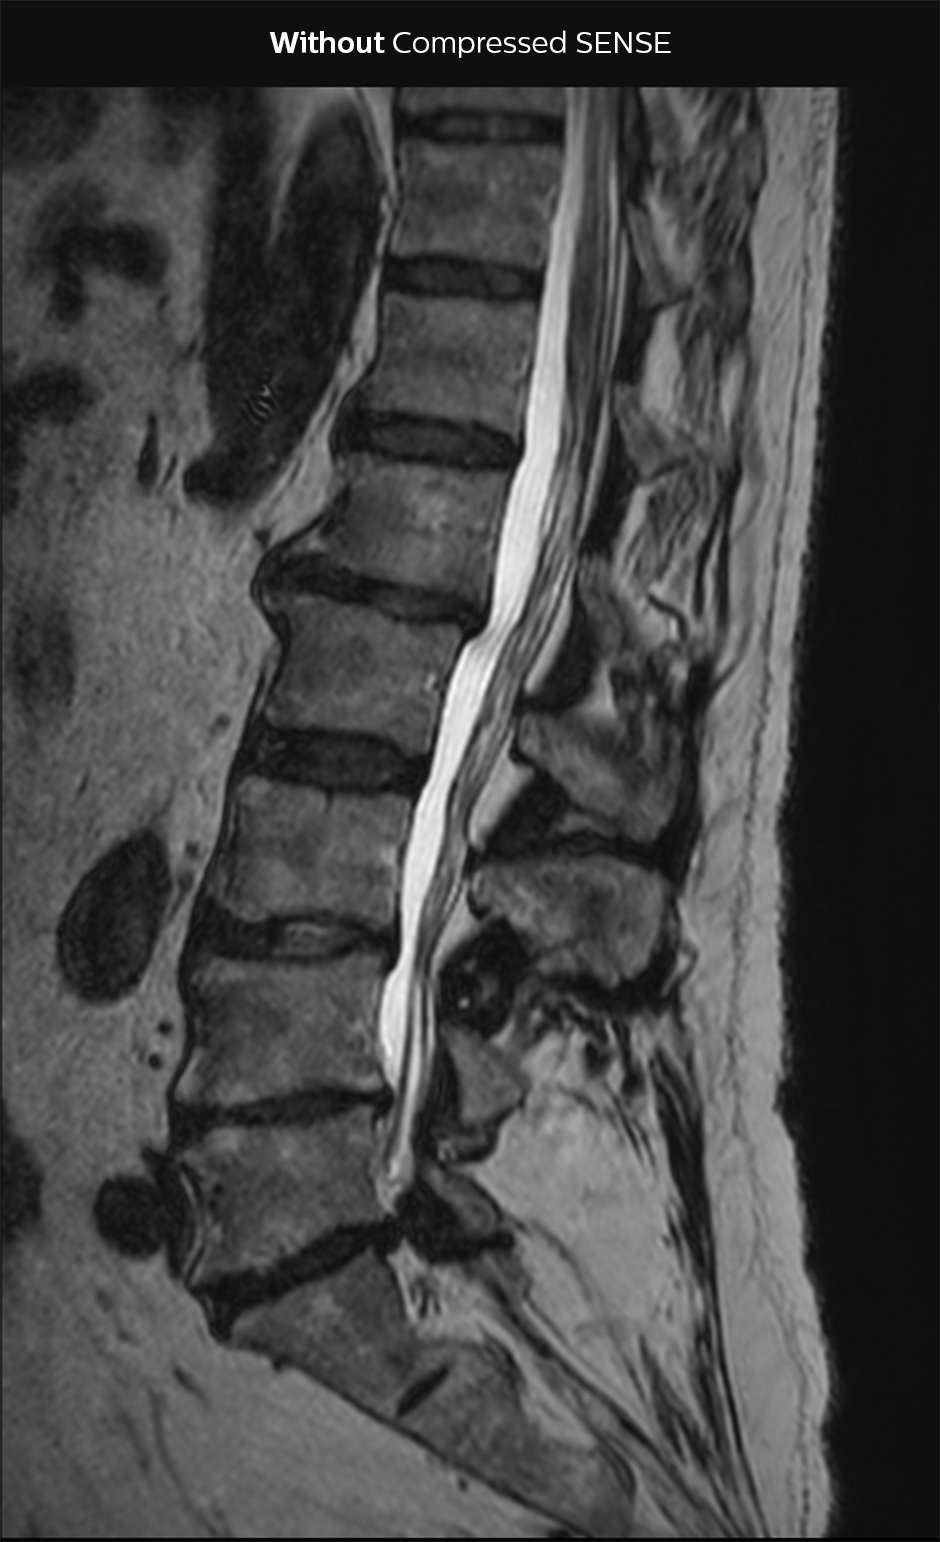

“Our aim for the spine is to use Compressed SENSE to help us make the switch to using 3D SpineVIEW. In lumbar spine, for example, we can reduce scan time for 3D T2W SpineVIEW by 27% to 4:46 minutes, voxel size 0.8 x 0.8 x 1 mm."

In this example Compressed SENSE has a 26% shorter scan time and improved spatial resolution simultaneously.

3D T2 SpineVIEW, scan time 6:29 min, voxel size 1 x 1 x 1.4 mm

3D T2 SpineVIEW, scan time: 4:46 min, voxel size 0.8 x 0.8 x 1 mm